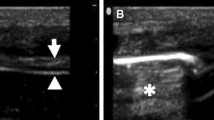

The patients were studied in the semi-recumbent position throughout the study. Ultrasonography was performed by two intensivists both experienced in ultrasonography, using an Envisor system (Philips Ultrasound, Bothell, WA) equipped with a high resolution 12 MHz ultrasound linear probe. Using the signal from the ventilator, airway pressure was displayed on the screen of the Echo-Doppler machine during NIV, ensuring accurate determination of the tracings relative to the respiratory cycle. Ultrasound recordings of diaphragm thickness were performed as previously reported [15]. Briefly, the diaphragm was located by placing the transducer in the intercostal space above the right 10th rib in the midaxillary or anteroaxillary line and directing the ultrasound beam perpendicular to the diaphragm (Fig. 1a). The zone of apposition was assessed at 0.5–2 cm below the costophrenic sinus. The inferior border of the costophrenic sinus was identified at end-inspiration as the zone of transition from the artefactual representation of normal lung (the lung sliding) to the visualization of diaphragm and liver. The diaphragm thickness was recorded in time motion (TM) mode. The sweep speed was adjusted as slow as possible to obtain a minimum of three cycles on the same image. The diaphragm was outlined by the two clear bright parallel lines of the pleural and peritoneal membranes (Fig. 1b and Online Videos). Several images were recorded and images were deemed invalid if the two clear bright parallel lines of the pleural and peritoneal membranes were not plainly identified at each moment of the respiratory cycle. Ultrasonographic recordings were stored on compact disks, and a subsequent computer-assisted quantitative analysis was performed by a trained investigator who was unaware of the ventilatory condition. The measurements included diaphragm thickness at end-expiration (T EE) and at end-inspiration (T EI). When airway pressure could not be displayed on the screen of the Echo-Doppler machine to match the ultrasound tracings to the respiratory cycle (during SB), T EE was measured just before the thickening start and T EI was measured at maximal thickening. Measurements were averaged out of three or more consecutive breaths on the last valid image recorded at the end of each period. The thickening fraction (TF) was calculated as (T EI − T EE)/T EE and expressed as a percentage (Fig. 1c).

Probe placement to explore the diaphragm in the zone of apposition (a), with the ultrasonographic view of the normal diaphragm in the zone of apposition (b) and illustration of the measurement of diaphragm thickness at end-inspiration and end-expiration in TM mode (c). T EI thickness at end-inspiration, T EE thickness at end-expiration